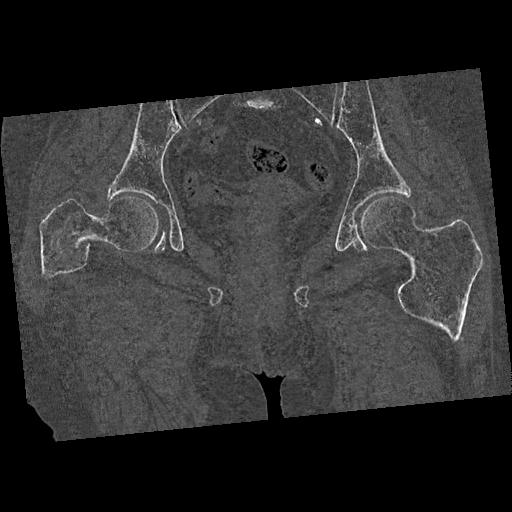

100703 1/27 両股正面+軸 1/29 両股正面+軸 94歳女性 パンソンロン